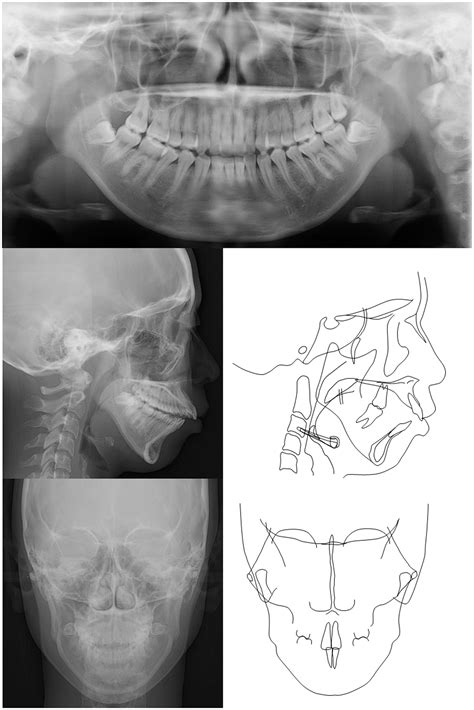

To confirm a diagnosis of Idiopathic Condylar Resorption, specialists use a multi-faceted approach. A physical exam is rarely sufficient; advanced imaging is essential. A Cone Beam Computed Tomography (CBCT) scan is the gold standard for visualizing the condylar heads and determining the extent of bone loss. MRI scans may also be utilized to evaluate the condition of the articular disc within the joint. By comparing serial radiographs over several months, an oral and maxillofacial surgeon can track the rate of resorption to determine if the condition is currently active or stable.

The progression of ICR can lead to significant changes in a person’s bite and facial profile. As the condyle shrinks, the lower jaw (mandible) shifts backward and upward, often resulting in an anterior open bite, where the front teeth no longer meet even when the back teeth are touching. This change can occur rapidly or slowly, often causing distress to patients who notice their smile or facial structure shifting unexpectedly.

One of the most critical aspects of treatment is timing. If a surgeon performs corrective surgery while the resorption is still active, there is a high risk that the new jaw position will not be maintained, and the bone will continue to resorb post-operatively. Therefore, proving clinical stability through serial imaging is a mandatory precursor to any surgical intervention.